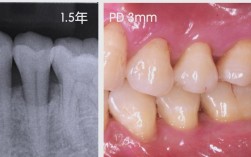

- 临床检查:通过牙周探诊测量牙周袋深度、附着丧失,结合X线片或CBCT评估骨缺损的类型、范围和程度。

- 定期复诊:术后1周拆线,3个月、6个月复查CBCT,评估骨愈合情况(植骨材料与自体骨融合通常需3-6个月)。